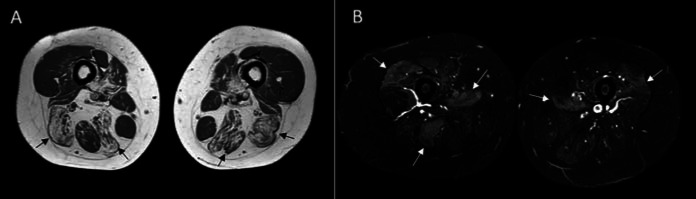

Pompe disease is a rare metabolic disorder that is characterized by the deficiency of the acid aglucosidase. As a result, glycogen accumulates in several tissues including motor neurons, skeletal, cardiac, and smooth muscles. The course of the disease varies according to the type of mutations, and the clinical phenotype can be affected by the enzyme levels. Late-onset Pompe disease (LOPD) is a challenging issue for clinicians as it has a milder phenotype with later onset of symptoms and slower disease progression. One of the most important differentials in the diagnosis of LOPD is inflammatory myositis as both diseases have some common clinical and laboratory features. Herein, we presented a 30-year-old female patient initially diagnosed as polymyositis and treated with immunosuppressive therapy without a benefit on her symptoms and later diagnosed as LOPD.